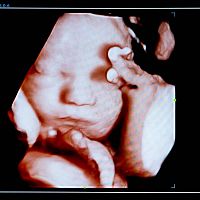

2D, 3D alebo 4D ultrazvuk

„Povinné“ prenatálne ultrazvuky sa robia 2D formou, stačí to na zistenie všetkých potrebných údajov, ktoré lekár potrebuje zistiť o plode. Ide o hlavný diagnostický nástroj pri ultrazvukovom vyšetrovaní. 3D ultrazvuk predstavuje statické zobrazenie plodu, avšak v priestore. Trojrozmerný obraz sa dosahuje počítačovým spracovaním súboru nakumulovaných 2D obrazov. Ďalšou môžnosťou je 4D zobrazenie, ktoré sa od plastického 3D obrazu líši jedným faktorom navyše – časom/pohybom. Snímku vidíte v priamom prenose, môžete sledovať, ako sa dieťa hýbe a sledovať jeho mimiku. 3D a 4D ultrazvuky nie sú bezplatné.